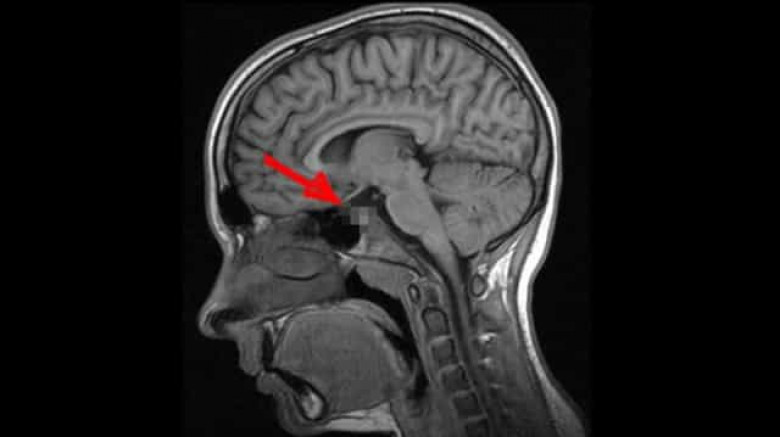

2009 թ. գիտնականները որոշեցին լրջորեն ուսումնասիրել այս ոչ սովորական երևույթը: Որոշ ժամանակ անց Մասաչուսեթսի տեխնոլոգիական համալսարանի մասնագետները հայտարարեցին, որ ուղեղն ունի այնպսիս հատված, որը պատասխանատու է այս երևույթի համար: Դեժավյուի գլխավոր դերը այն նեյրոններինն է, որոնց շնորհիվ կարողանում ենք զգալ պատկերների ամենափոքր տարբերություններն անգամ: Սրա շնորհիվ մարդը գիտակցում է, թե ինչպիսի տպավորություններ է ինքը վաղուց արդեն ստացել, իսկ որոնք են ամբողջապես նոր նրա համար: Այսն կարծես մարդու «կյանքի փորձառությունը» բաժանում է անցյալի և ներկայի: Սակայն երբ երկու տպավորություններ իրար շատ նման են լինում, ուղեղի այդ հատվածի աշխատանքը «կախում է», ինչն էլ բերում է տարօրինակ այս զագցմանը:

2009թ. բացահայտումից հետո միայն մեկ անպատասխան հարց է մնացել՝ այս երևույթը բնորոշ է առողջ մարդկա՞նց, թե՞ ոչ այնքան: Պատասխանը գտնելու պատասխանատվությունն իրենց վրա վերցրին Չեխիայի Մասարիկա և Մեծ Բրիտանիայի Էկսետերի համալսարանների մասնագետները: Նրանք պարզեցին, որ դեժավյու կարող է լինել անգամ փոքր տարիքում, երբ նոր կազմավորվում է ուղեղը: Հոգնախության և սթրեսի ժամանակ ուղեղի տվյալ հատվածի աշխատանքը խաթարվում է և արդյունքում առաջանում են հիշողություններ այնպիսի բաների մասին, որոնք երբեք չեն էլ եղել: Գիտնականների վերջնական դիագնոզը ցավալի է՝ դեժավյուն համարվում է նյարդաբանական խանգարում: